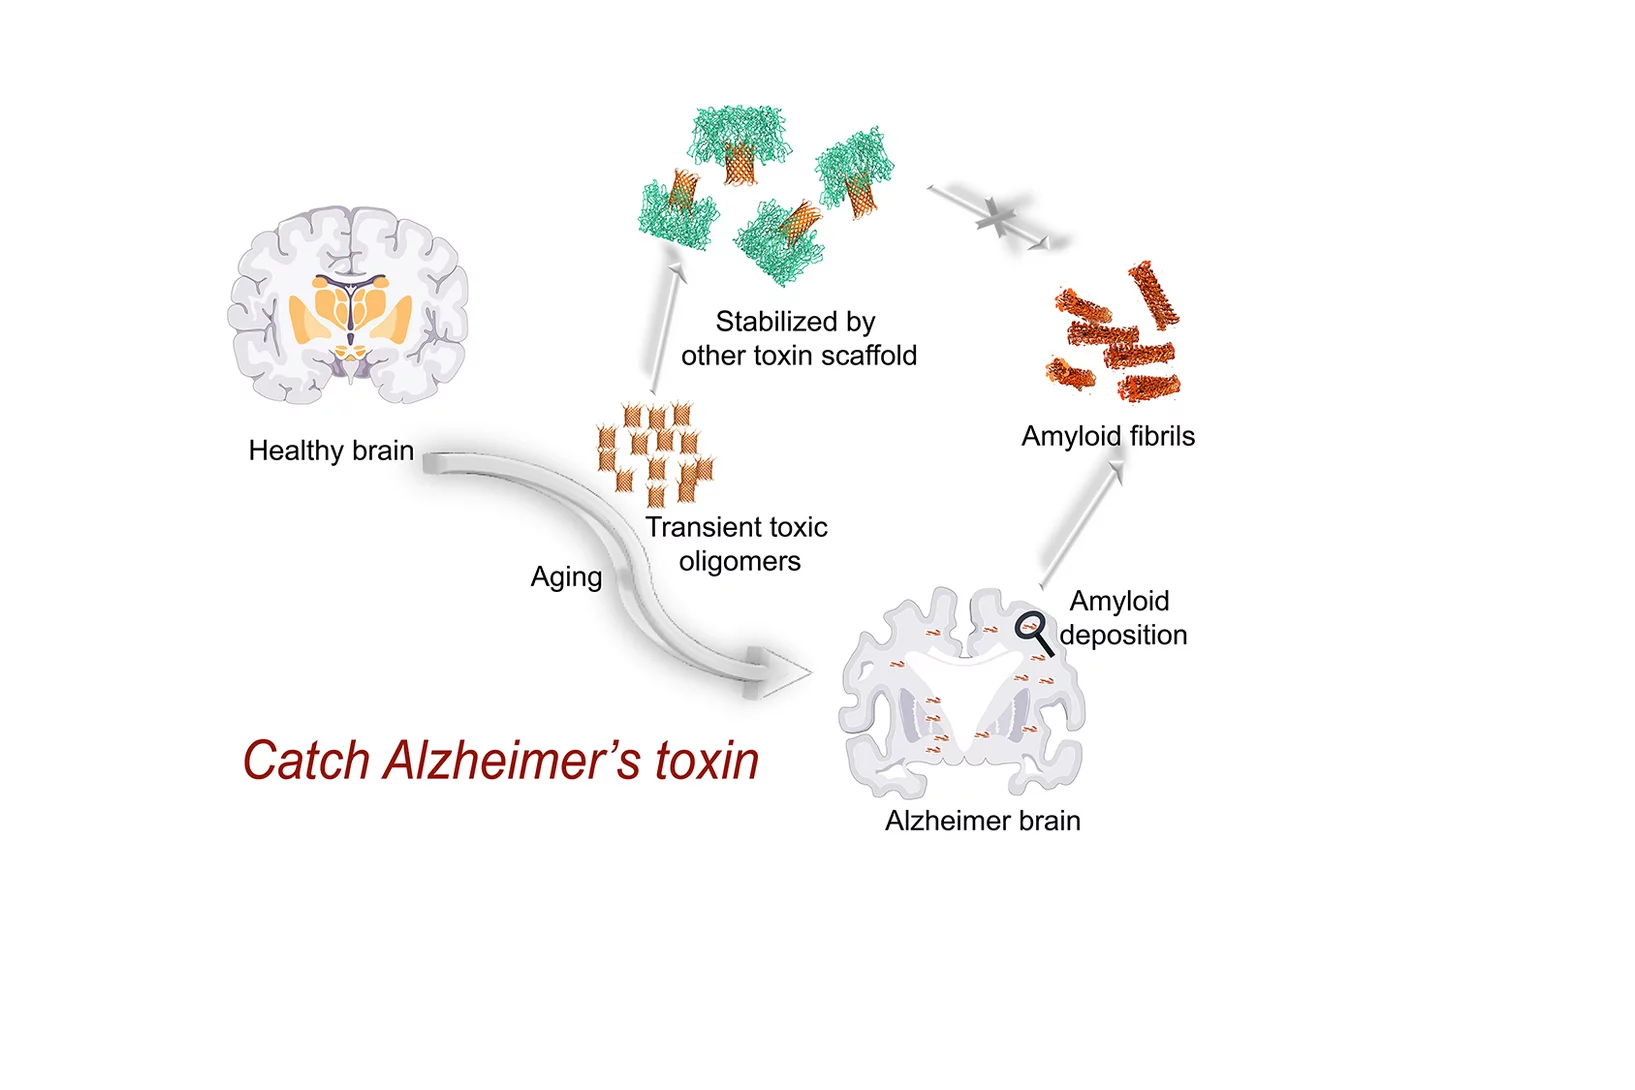

Nanobodies against SARS-CoV-2

In a study published in EMBO Journal, researchers at the Max Planck Institute for Biophysical Chemistry, Göttingen, Germany, developed nanobodies that efficiently block the coronavirus SARS-CoV-2 and its variants. The high resolution structural characterization was performed at the X10SA crystallography beamline at the Swiss Light Source.